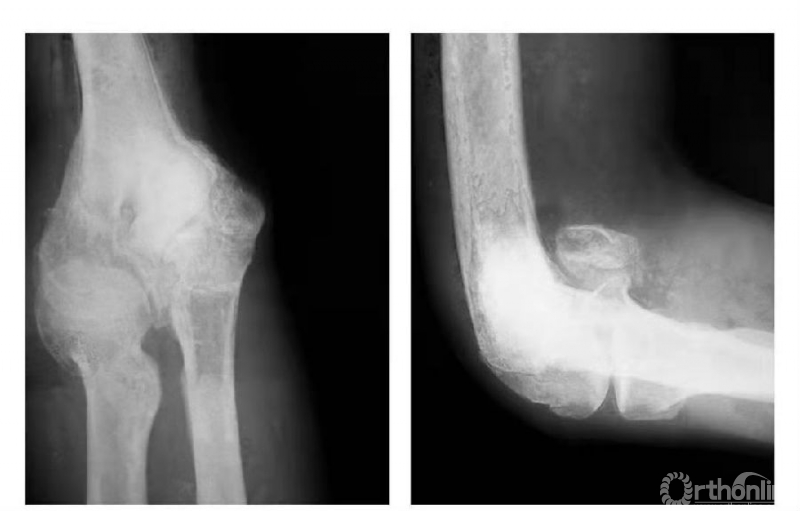

二、陈旧性内髁骨折

例1:肱骨内髁滑车关节面骨折,骨块陷入鹰嘴窝内,致肘内翻畸形(图4)。

图4

例2:肱骨内髁滑车关节面骨折,骨块嵌夹在尺肱关节间,且有翻转现象(图5)。

图5